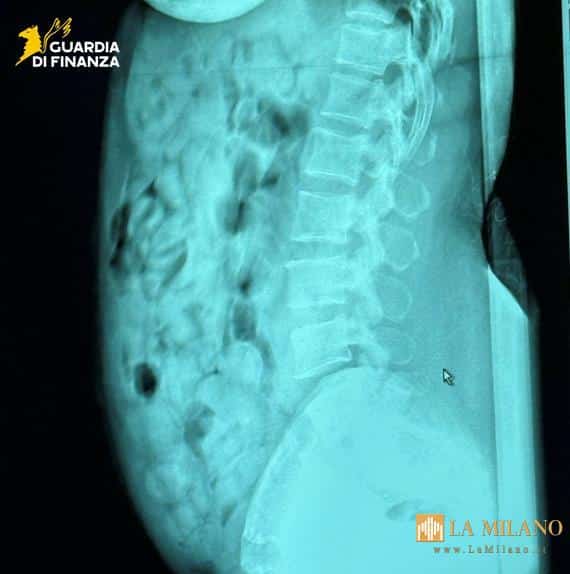

I successivi esami radiologici svolti presso l’ospedale “Papa Giovanni XXIII” di Bergamo hanno confermato che la viaggiatrice aveva ingerito 120 ovuli in contenitori plastici rigidi avvolti in strati di nastro adesivo i quali, una volta analizzati, sono risultati contenere sostanza stupefacente del tipo eroina, per complessivi 1.393 grammi.